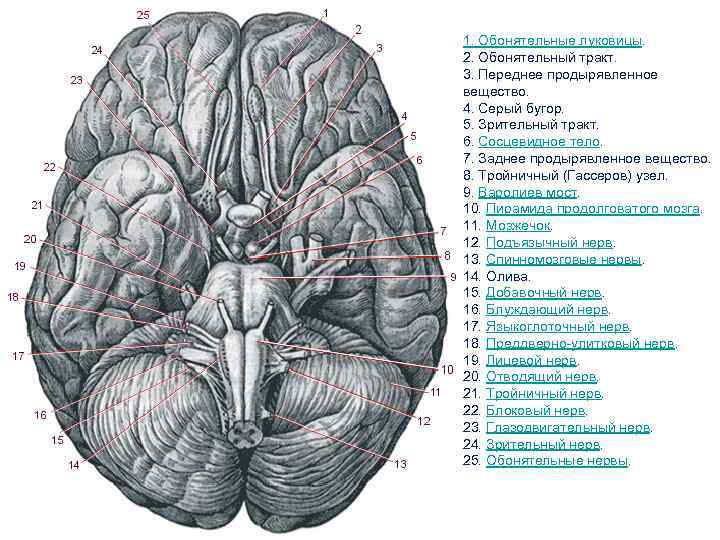

1. Обонятельные луковицы. 2. Обонятельный тракт. 3. Переднее продырявленное вещество. 4. Серый бугор. 5. Зрительный тракт. 6. Сосцевидное тело. 7. Заднее продырявленное вещество. 8. Тройничный (Гассеров) узел. 9. Варолиев мост. 10. Пирамида продолговатого мозга. 11. Мозжечок. 12. Подъязычный нерв. 13. Спинномозговые нервы. 14. Олива. 15. Добавочный нерв. 16. Блуждающий нерв. 17. Языкоглоточный нерв. 18. Преддверно-улитковый нерв. 19. Лицевой нерв. 20. Отводящий нерв. 21. Тройничный нерв. 22. Блоковый нерв. 23. Глазодвигательный нерв. 24. Зрительный нерв. 25. Обонятельные нервы.

1. Обонятельные луковицы. 2. Обонятельный тракт. 3. Переднее продырявленное вещество. 4. Серый бугор. 5. Зрительный тракт. 6. Сосцевидное тело. 7. Заднее продырявленное вещество. 8. Тройничный (Гассеров) узел. 9. Варолиев мост. 10. Пирамида продолговатого мозга. 11. Мозжечок. 12. Подъязычный нерв. 13. Спинномозговые нервы. 14. Олива. 15. Добавочный нерв. 16. Блуждающий нерв. 17. Языкоглоточный нерв. 18. Преддверно-улитковый нерв. 19. Лицевой нерв. 20. Отводящий нерв. 21. Тройничный нерв. 22. Блоковый нерв. 23. Глазодвигательный нерв. 24. Зрительный нерв. 25. Обонятельные нервы.